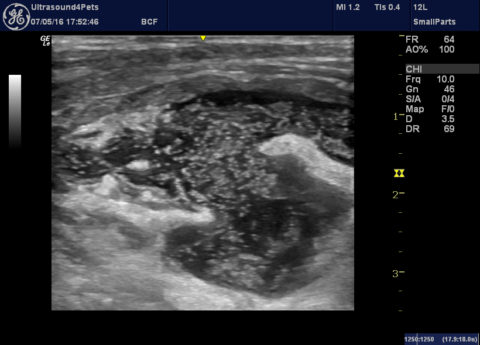

Another anaphylactic shock dog

This is my own dog -I’m feeling able to write this now that he’s recovered fully. As previously discussed anaphylaxis is a phenomenon which can be difficult to document definitively. However, like the last case which I wrote up a few weeks back this involved a previously 100% healthy dog with a wasp/bee chasing habit … Continue reading